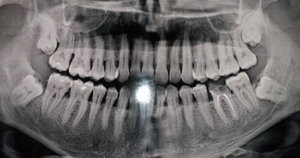

Разошлось мнение двух врачей: одна считает, что кариес на шестнадцатом есть, вторая, что его нет. На рентгене, на шестнадцатом виден темный участок, то есть, скорее кариес есть, чем его нет.

С вашей точки зрения он скорее есть, чем его нет? (речь идет не о поверхностном кариесе, который на рентгене нельзя увидеть, а о более глубоком: среднем или глубоком). Снимок был сделан до лечения.

На снимке в области семнадцатого и двадцать шестого зуба, под пломбой, наблюдается полость, которая неграмотно препарирована перед установкой пломбы, чувствительность и некий дискомфорт при надкусывании или пережевывании твердой пищи связано именно с этим. Что касается шестнадцатого зуба, я считаю, что полость имеется, но все-таки необходим еще и очный прием.